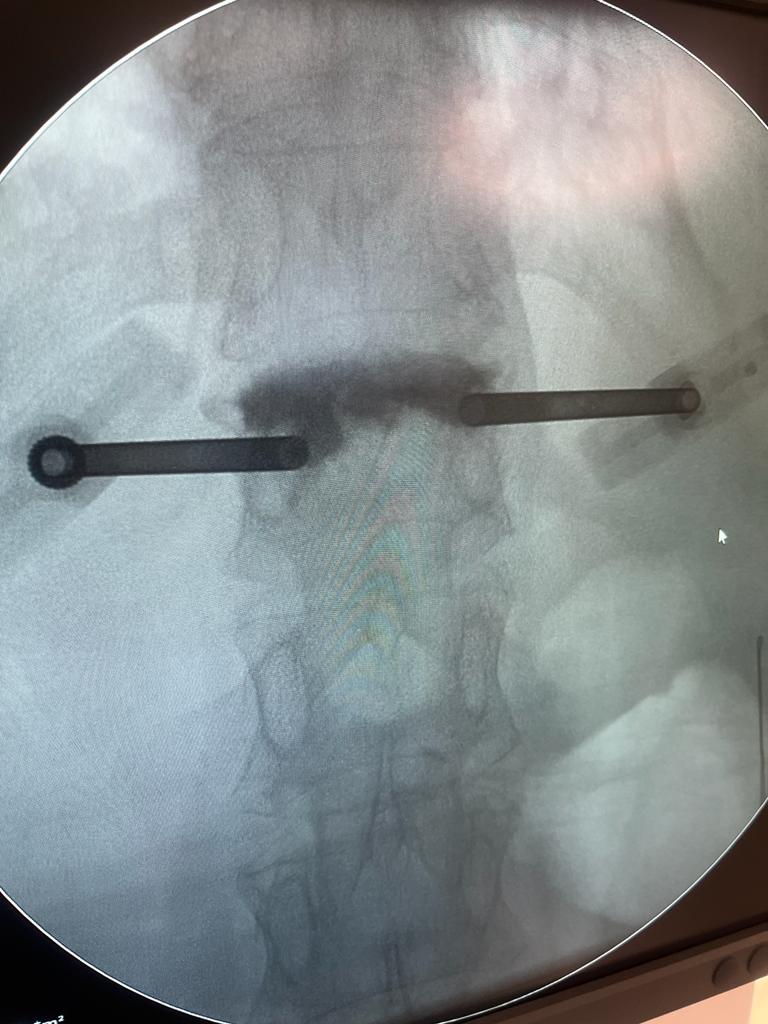

La cementación vertebral es un tratamiento contra el dolor, que consiste en introducir de manera percutánea cemento dentro de una vértebra fracturada, a través de una cánula. Previamente se intenta la corrección de la deformidad vertebral mediante el uso de unos balones hinchables.

Es un procedimiento mínimamente invasivo, se realiza en quirófano de forma ambulatoria, generalmente bajo sedación y anestesia local. Se emplean incisiones de menos de 5mm sobre la vértebra . Utilizando un balón que se introduce a través de una cánula, para crear una cavidad dentro de la cual se inyecta el cemento.